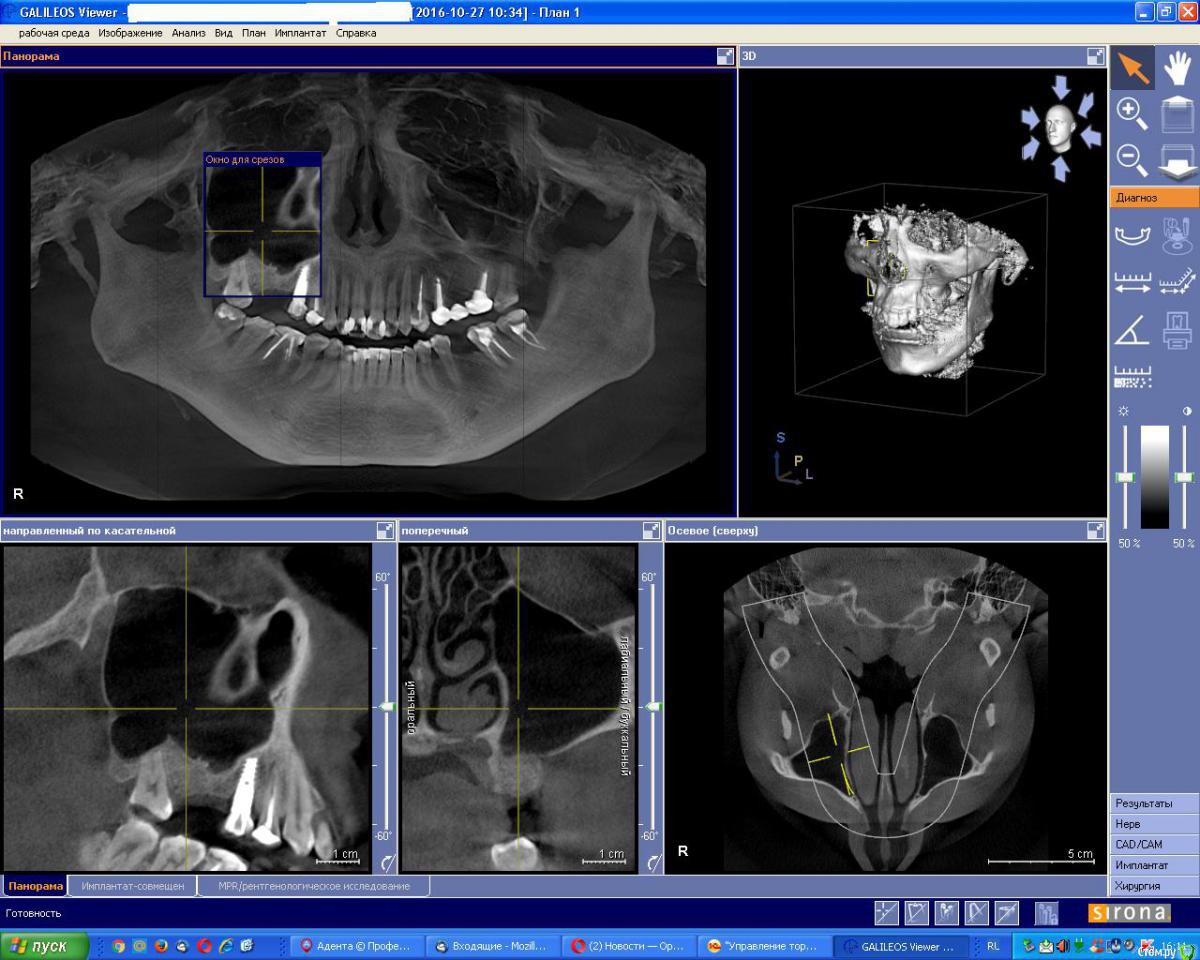

Evikrol Опубликовано 24 января, 2017 Поделиться Опубликовано 24 января, 2017 http://s020.radikal.ru/i708/1701/b4/40b7ad6d4617.jpg http://s008.radikal.ru/i305/1701/4f/017eeafd9c8c.jpg Синуслифтинг с одномлментной имплантацией 14 декабря. Операция без особенностей, мобилизация лоскута, ушивание без натяжения. Возможно проглядел неудовлетворительную гигиену, брекеты. Флемооклав, мирамистин, нимесил, полидекса. Через неделю швы частично разошлись, пациент отметил что был сильный отёк. Обработал и назначил метрогил. 15 января принёс имплантат в руках, говорит и графт тоже выпал. КТ от 24 января. Вопрос: Какова тактика ведения, как успокоить слизистую гайморовой? Всем заранее спасибо. Ссылка на комментарий

Evikrol Опубликовано 26 января, 2017 Автор Поделиться Опубликовано 26 января, 2017 Пазуха могла быть "чистой", но соустье узким. После вмешательства слизистая увеличилась в объёме и просвет закрылся. Кстати, об отсутствии адекватного дренажа косвенно говорит и КТ-срез..Что же делать если естественное соустье узкое, это противопоказание к синуслифтингу? Ссылка на комментарий